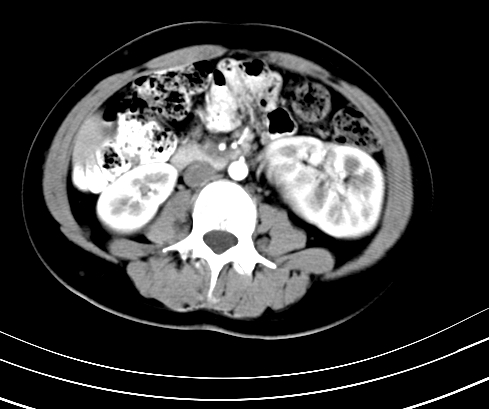

动脉期